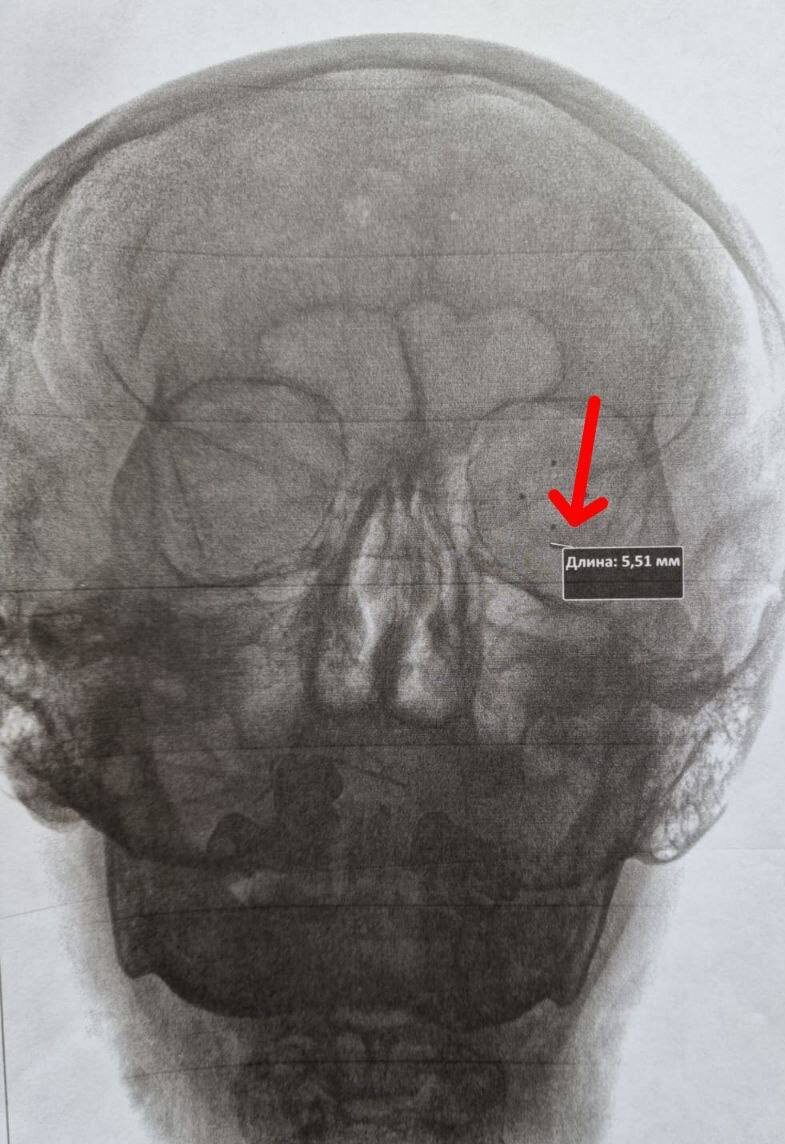

Врачи диагностировали проникающее ранение роговицы и склеры с инородным телом размером около 5 мм. В экстренном порядке была проведена обработка раны и удаление неизвестного предмета. Чтобы сохранить зрение, пациенту потребовалась дополнительная операция.